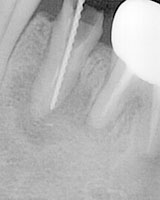

患者様は歯ぐきの腫れを繰り返しているということで治療を開始しました。

レントゲン写真を撮ってみると、歯の根の先が黒くなり、骨が溶けているのがわかりました。

歯の中に器具を入れてみると、歯の中で元々の道筋とは違うところに器具が通っていくのがわかりました。

器具を入れると白い器具が根っこの右にそれているのがわかります。

通常はまず抜歯する例ですが、患者さまと話し合い、出来るだけ保存する方法を選びました。

まず神経の治療を元々の道と穴があいているところ、両方に対して行いました。

途中で薬が二つに分かれていくのがわかります。